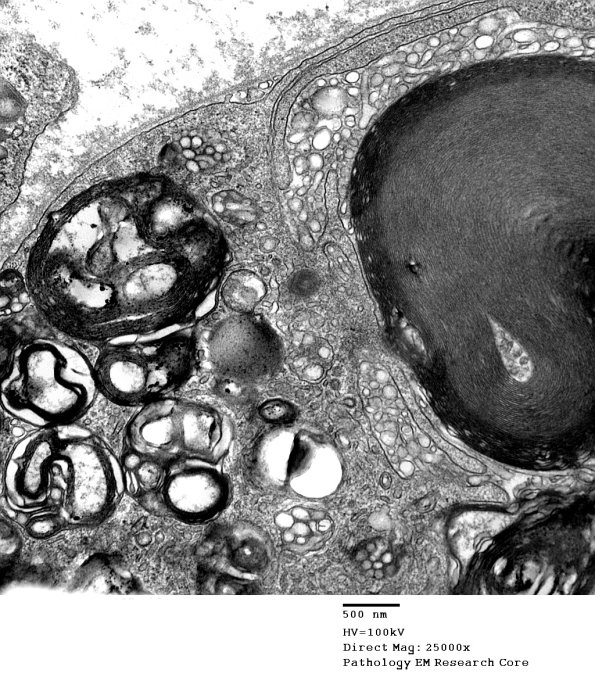

Several patterns of myelinopathy are noted including vesicular myelin change. (electron micrographs)